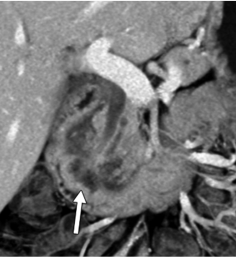

- A. Circumferential irregular submucosal wall thickening noted in D2 and D3 segment of duodenum causing luminal narrowing.

- B. Few hypoenhancing areas within the medial wall of duodenum. Uncinate process of pancreas appears oedematous.

- C. Contrast is seen passing from the duodenum into the jejunum. No contrast leakage noted.